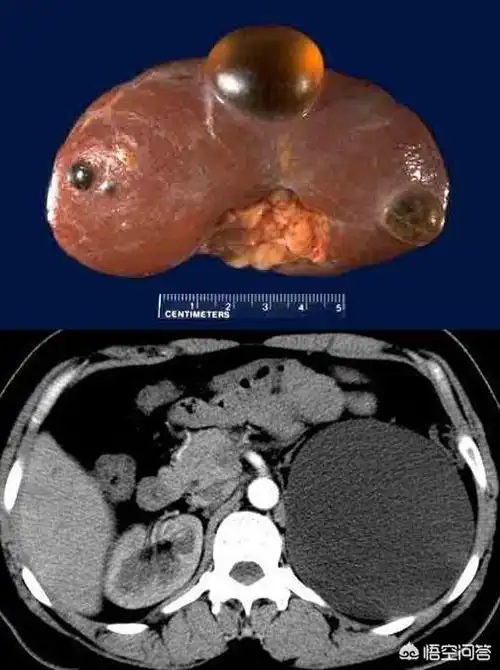

肾囊肿

肾囊肿分单纯性和获得性!